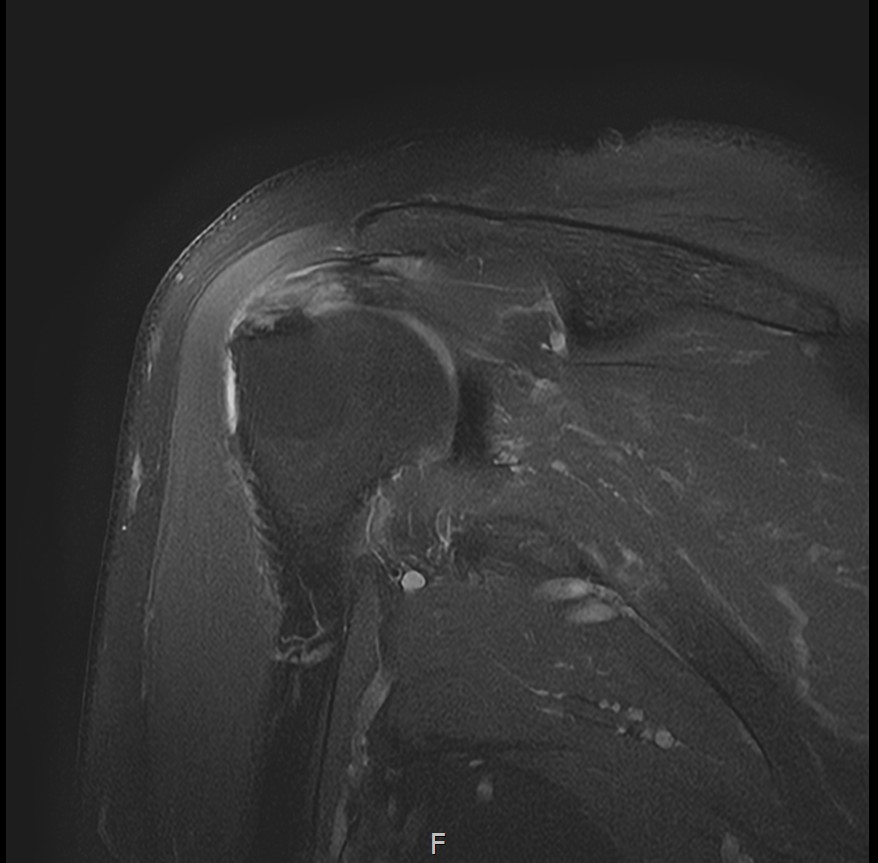

진단 결과:

- ✓관절면측 부분파열: 약 35%

- ✓근육 위축이나 지방 변성은 없음 (젊은 나이)

10주 후 초음파:

봉합 부위가 정상 인대처럼 하얗게 재생되어 있었습니다. 골수자극의 효과로 예상보다 빠른 재생이 확인되었습니다.